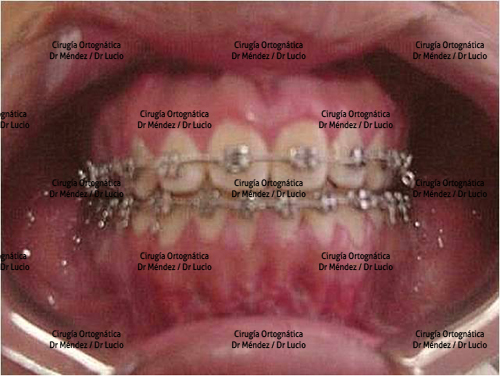

HIPOPLASIA MAXILAR Paciente operado de avance maxilar |

||